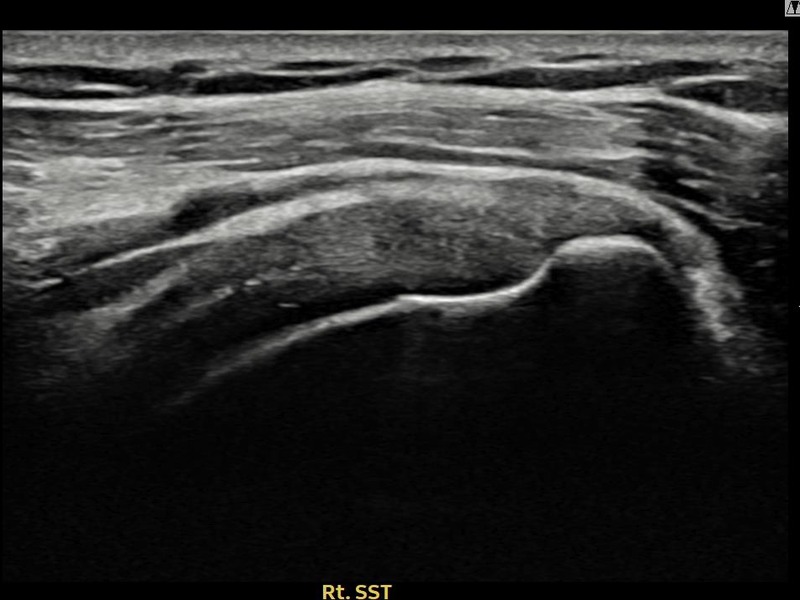

최ㅇㅇ님 · 우측 극상근건 관절면측 부분파열

우측 어깨 통증으로 수면과 일상 동작이 어려워 내원하셨습니다. 초음파 유도 하 축소봉합술 후 힘줄 연속성이 회복되었습니다.

상세 보기 →